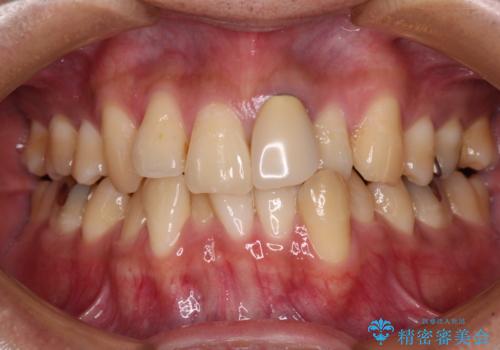

前歯のがたつきをなおしたい マウスピース矯正

担当医 大元洋佑

![[ マウスピース矯正 ] 前歯の角度・がたつきを治したい。の症例 治療前](https://seimitsushinbi.jp/wp/wp-content/uploads/2024/02/IMG_7820-500x350.jpg?v=1707810350)

![[ マウスピース矯正 ] 前歯の角度・がたつきを治したい。の症例 治療後](https://seimitsushinbi.jp/wp/wp-content/uploads/2024/02/8334681fa61954fc45ff8cef14f33166-500x350.jpg?v=1707810480)